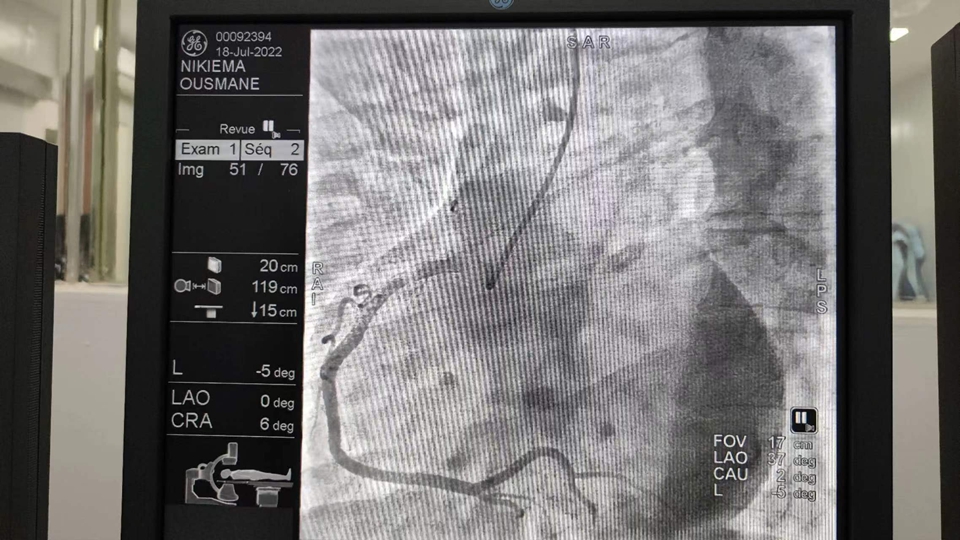

7月15日,我在门诊接诊了一名50岁的男性患者,因“反复胸闷3月”来医院就诊,患者有糖尿病和肺部疾病,当地Hippolyte SOME医生讨论病情后,考虑患者为冠心病,决定为患者施行冠状动脉造影术。

7月18日上午9点,我们为患者施行冠状动脉造影术检查,术中造影显示:患者心脏右冠管壁不光滑,左冠脉正常。经分析研判后,诊断为“冠状动脉粥样硬化”。9:40左右,手术顺利完成。